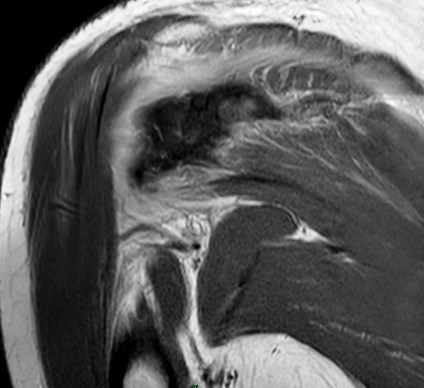

Figure 1 for case Stab wound

Figure 1

Discussion

Filled with hemorrhage. The infraspinatus took the brunt.